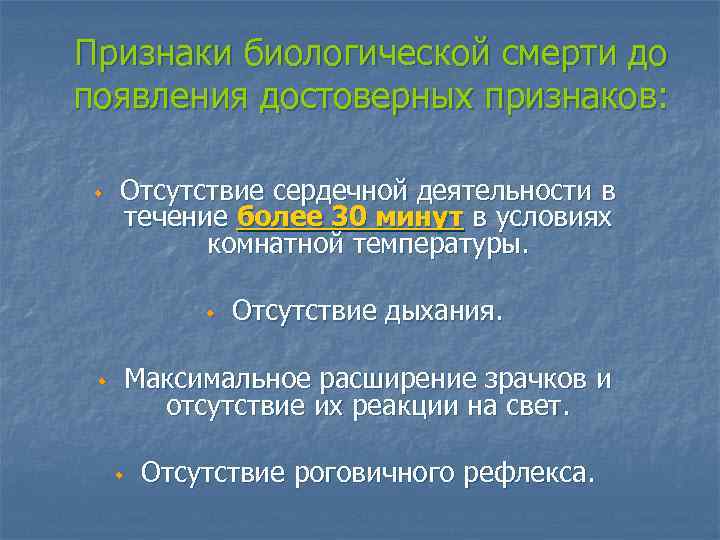

Смерть биологическая - необратимое состояние, при котором всякие попытки оживления оказываются безуспешными. ДОСТОВЕРНЫЕ ПРИЗНАКИ БИОЛОГИЧЕСКОЙ СМЕРТИ 1. Феномен кошачьего зрачка. Если надавить на зрачок пострадавшего, то он приобретает форму эллипса или узкой щели. 2. Трупные пятна - начинают формироваться через 2 -4 часа после остановки сердца. 3. Трупное окоченение - проявляется через 2 -4 часа после остановки кровообращения, достигает максимума к концу первых суток и самопроизвольно проходит на 3 -4 сутки.

Признаки биологической смерти до появления достоверных признаков: w Отсутствие сердечной деятельности в течение более 30 минут в условиях комнатной температуры. w w Отсутствие дыхания. Максимальное расширение зрачков и отсутствие их реакции на свет. w Отсутствие роговичного рефлекса.